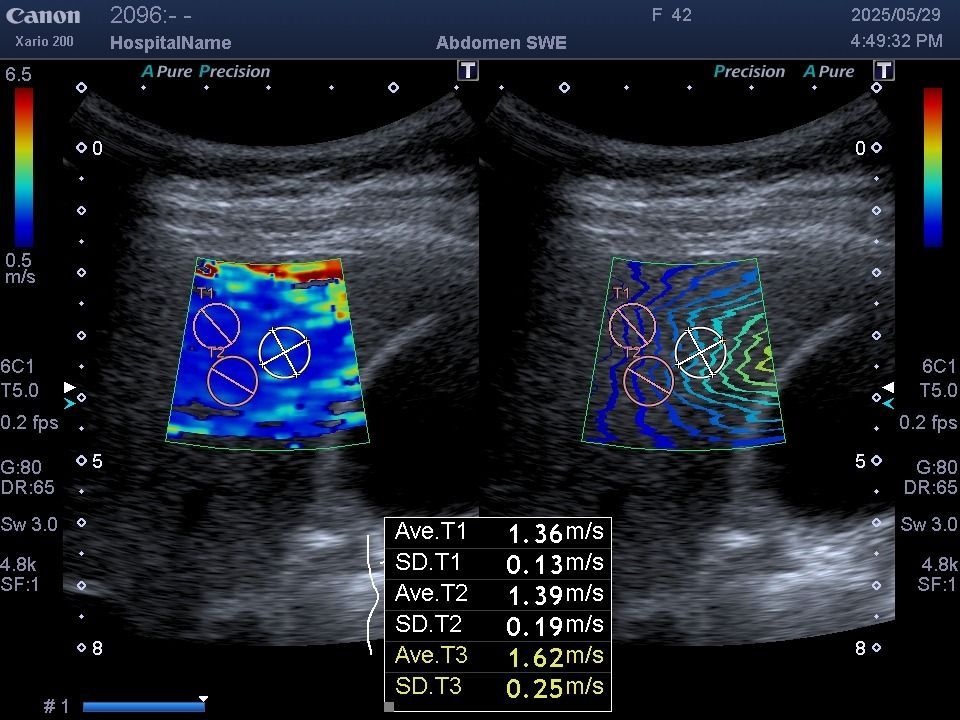

非侵入性肝纖維化超音波檢查

此檢查主要用來評估肝臟的硬度與脂肪含量

無需抽血或穿刺,是一種快速、無痛、非侵入性的肝臟評估工具

- 肝纖維化(fibrosis)

- 肝硬化(cirrhosis)

- 肝脂肪變性(steatosis)

非侵入性肝纖維化超音波特別適合

慢性肝病患者(B/C 肝炎、脂肪肝、酒精性肝病、自體免疫性肝病),以及

肝功能異常或有肝硬化風險的人。它能幫助醫師決定是否需要積極治療或加強追蹤。